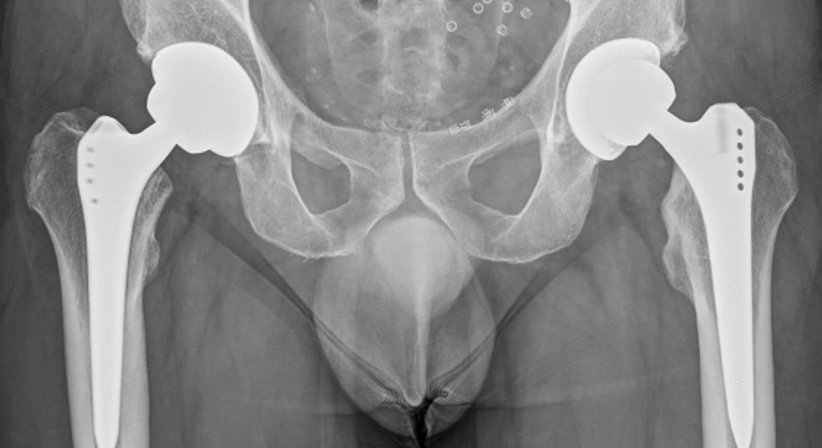

Bei Patienten mit fortgeschrittener Arthrose im Bereich der Hüfte (Coxarthrose), bei welchen es trotz Ausschöpfen unterschiedlicher konservativer Behandlungsmaßnahmen zu einem Fortbestehen der Beschwerden und einem Fortschreiten der degenerativen Veränderungen kommt, sollte die Implantation einer Hüftprothese (künstliches Hüftgelenk) durchgeführt werden. Dadurch wird der durch die Arthrose verursachte Schmerz beseitigt und die Beweglichkeit und Lebensqualität langfristig wieder hergestellt.

Neben Knieprothesen zählen Hüftprothesen, welche die Form und Funktion des natürlichen Hüftgelenks nachahmen, zu den am häufigsten implantierten Endoprothesen.

Bei der Wahl der implantierten Prothese kann man auf verschiedene Materialien und Designs zurückgreifen. Durch Gleitflächenpaarungen wie Keramik-Keramik können heutzutage sehr geringer Verschleiß und damit eine sehr lange Haltbarkeit erreicht werden. Die Verankerung der einzelnen Komponenten der Prothese im körpereigenen Knochen der Hüfte und des Oberschenkels erfolgt zementfrei (zementfreie Hüftprothese).